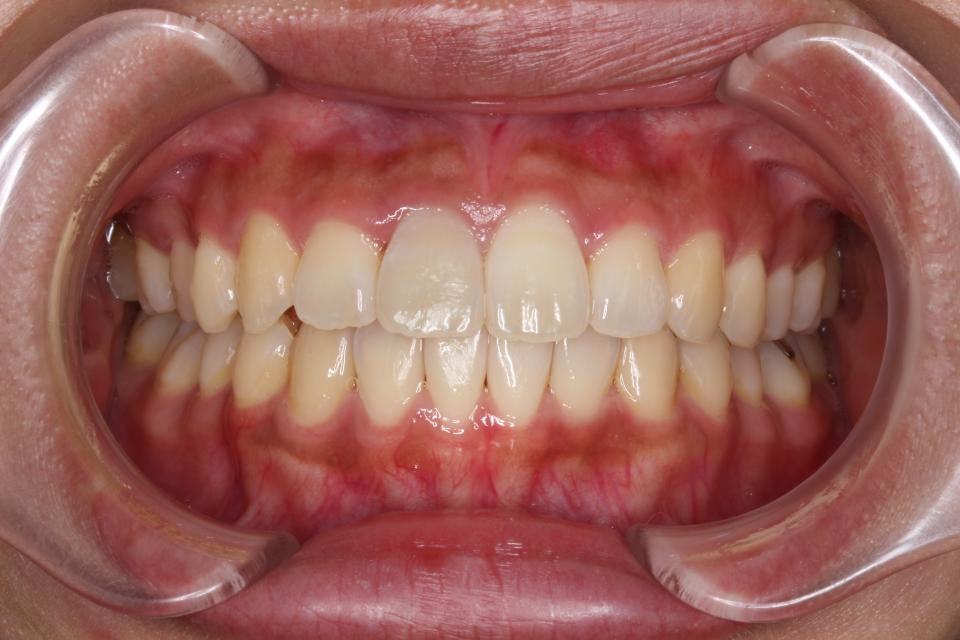

矯正治療後

現在は歯を動かす治療は終了し、マウスピース型のリテーナーをつけて

定期的にチェックしています。